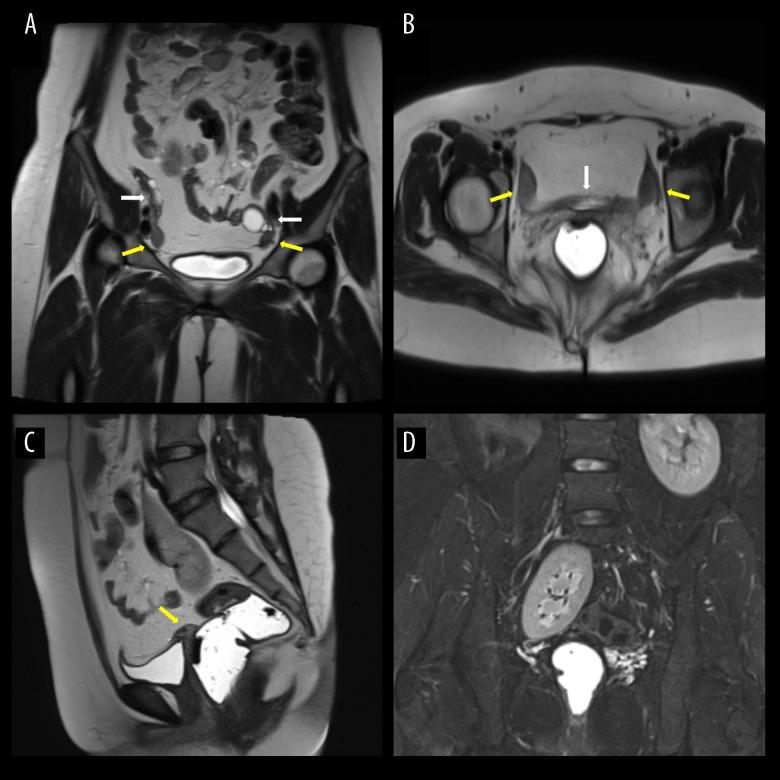

BACKGROUND Mayer-Rokitansky-Kuster-Hauser (MRKH) syndrome is a complex disorder of the female reproductive system that results in an absent uterus and vagina. MRKH syndrome can be an isolated anomaly (typical) or accompanied by other organ anomalies (atypical). Due to the similarity of symptoms with other congenital gynecological diseases, imaging modalities remain the most important tools in establishing the diagnosis by visualizing internal genital and detecting possible organ malformations. CASE REPORT We present a very rare case of a female with primary amenorrhea. Pelvic magnetic resonance imaging (MRI) showed the absence of a uterus and vagina with possible Mullerian remnants, as well as an incidental finding of a right ectopic kidney. Abdominal ultrasonography and chest X-ray showed that the patient also had situs inversus totalis. CONCLUSIONS MRKH syndrome may be associated with situs inversus totalis due to possible early embryologic malformations causing both conditions; however, the exact mechanism is still unknown. This report should serve as a more recent attempt to question whether situs inversus totalis is related to MRKH and to emphasize the importance of imaging modalities, especially MRI, in establishing the diagnosis of MRKH syndrome and the associated malformations.

我们介绍了一例女性原发性闭经的极罕见病例。盆腔磁共振成像(MRI)显示子宫和阴道缺失,可能有苗勒管残余物,以及右侧异位肾的意外发现。腹部超声和胸部 X 线检查显示患者还患有全内脏转位。